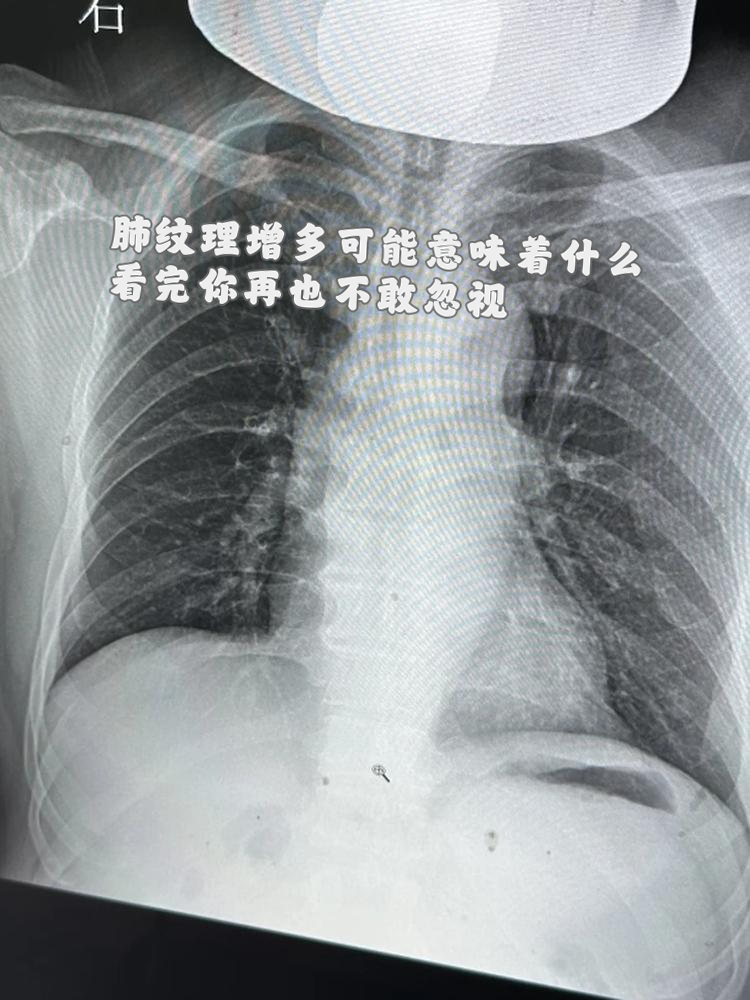

看完你再也不敢忽视!

很多女性在进行胸部 x 光或 ct 检查后,会被告知存在肺纹理增多的